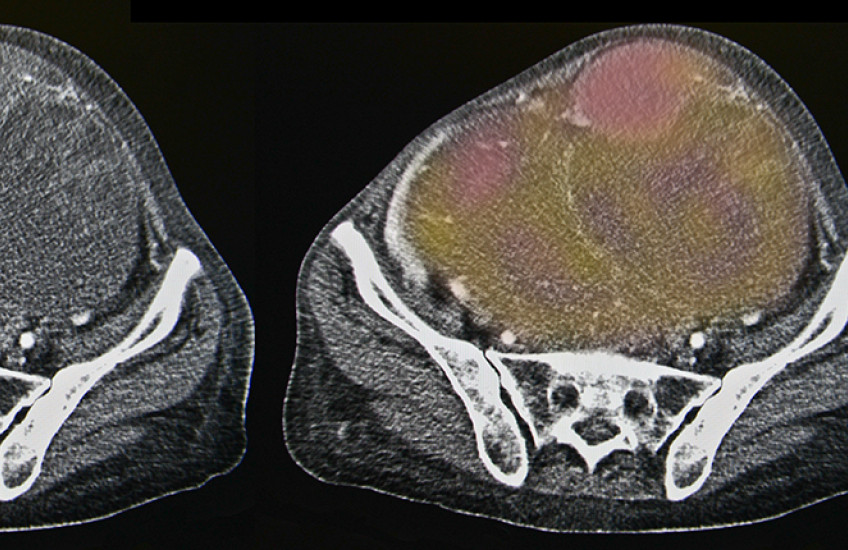

“The extracellular matrix itself can keep high-molecular-weight drugs from penetrating tumors, and angiotensin signaling contributes to matrix formation,” Xu said. “Since levels of an important enzyme in the angiotensin pathway are elevated and associated with poor outcomes in ovarian cancer, we investigated whether use of losartan to decrease fibrosis could improve outcomes in animal models of ovarian cancer.”

· Losartan treatment reduced extracellular matrix content and solid stress in ovarian tumors, increasing blood supply, oxygen levels and drug delivery.